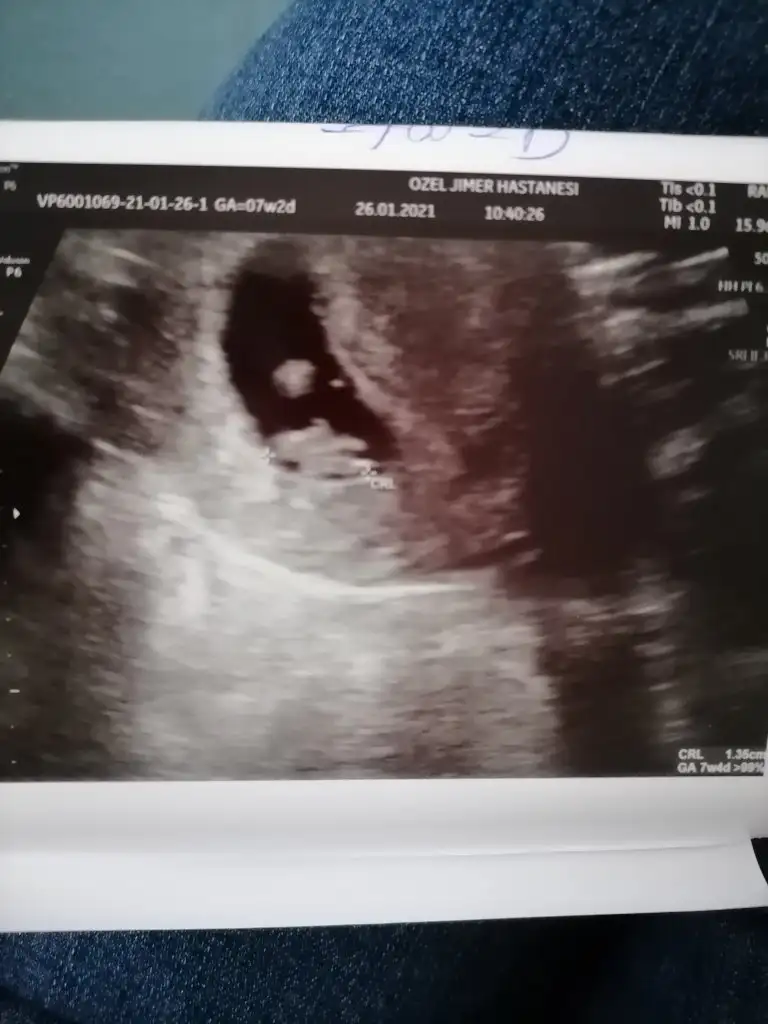

Gittim canım dr a ama çok iç açıcı değil şuan durum kese var ama bebişi görmedik kendi dr um erken dönemde olabiliyor böyle dedi 10 gün sonra tekrar gitcem. Moralim bozuldu çook 7+3 teyim şuan 21 aralıkta transfer oldu 25 aralık gibi tutunsa şuan 4 haftalık 2 hafta geri gittiğimde 6 hafta yapıyor valla aklım çok karıştı beklemekten başka çarem yok

İnşallah öyledir hayatım en iyisini rabbim bilir geçenki kontrole göre kese büyümüş ama bebişş hala yok nasip artık bekliycez

İlk oglumda 7+6 da kalp atisi yoktu. Tam bir hafta sonra 8+6 da kalp atisini duymustuk. Gec olusmustu. Belki boyle bir durumdur. İnsallah guzel haberler alirsin canim